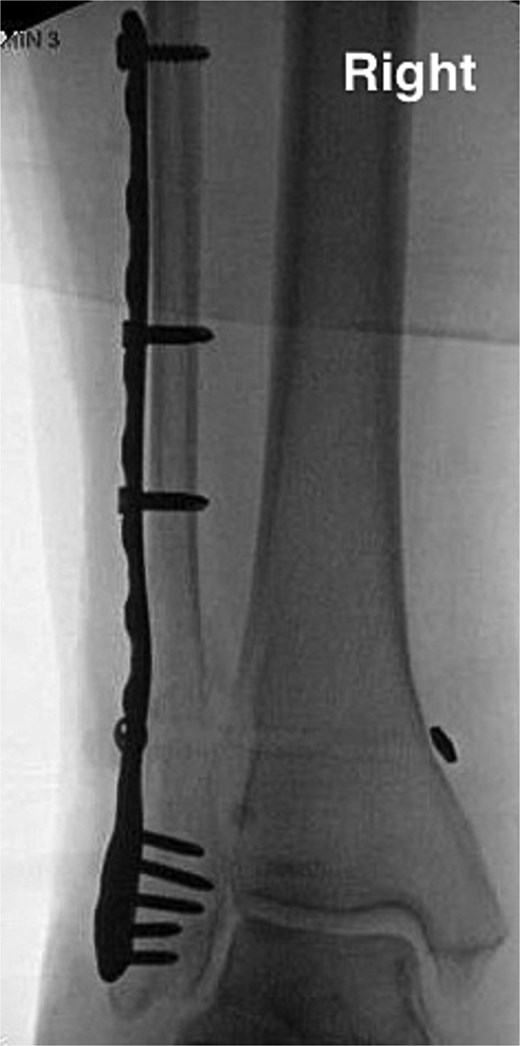

The lateral malleolus Weber C fracture was subsequently reduced to anatomical position. A locking stainless-steel plate was pre-contoured for the patient’s fibula and placed along the right lateral malleolus. Two 3.5 mm fully threaded bi-cortical locking screws were placed above the fracture and another 3.5 mm fully threaded bi-cortical locking screw was placed at the proximal end of the plate. A total of five 2.7-mm uni-cortical locking screws were used for fixation below the fracture site. Fluoroscopic images of the right ankle were taken in three views with simulated weight bearing in order to confirm anatomic alignment of the lateral malleolus Weber C fracture with proper plate and screw fixation. The syndesmosis was stressed in order to assess deltoid ligament function which showed widening. The distal tibiofibular joint was debrided and a king tong clamp was placed across the tibia and fibula through the fibular plate. Dorsiflexion of the ankle and hanging the posterior heel off a bump was done to avoid any anterior drawer effects on the ankle; following such, a tightrope was placed. Following final imaging (Fig. 3), the wound was then closed in layers.

Anterior–posterior post-operative X-ray demonstrating fixation of right Weber C fibular fracture.